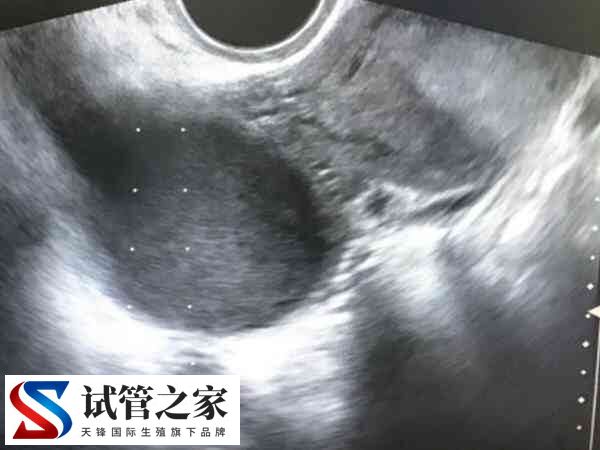

子宫内膜异位症指有活性的内膜细胞种植在子宫内膜以外的位置,而形成的一种女性常见妇科疾病,一般来说,该疾病表现的症状为痛经、月经异常、不孕和性交疼痛等。虽然会影响生育能力,但是可以通过试管婴儿实现生育。

根据以往子宫内膜异位患者做试管成功案例来看,对于子宫内膜异位患者,是可以通过试管婴儿技术怀孕,但最终能不能成功,这个具体需要看女性身体情况及医生操作水平,一般来说,患有子宫疾病的女性做试管比普通女性做试管的成功率要低很多。